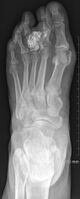

Bizarre parosteal osteochondromatous proliferation, middle finger

Bizarre parosteal osteochondromatous proliferation (BPOP) is a type of non-cancerous bone tumor belonging to the group of cartilaginous tumors.[1][4] It is generally seen in the tubular bones of the hands and feet,[5] where it presents with a rapidly growing 1-3cm painless lump, usually in a finger or toe.[1][2]

Medical imaging usually shows a well-defined wide-based bony growth on the surface of bone.[5] It can be pedunculated and irregular, giving it a "bizarre" appearance, and is not connected to underlying bone.[2]